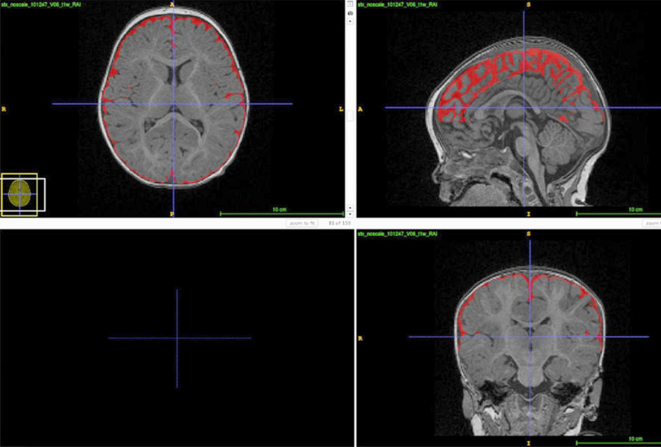

Drain bouché : L'excès de liquide céphalorachidien pourrait indiquer que le liquide ne circule pas bien, ce qui pourrait exposer le cerveau en développement à des molécules de déchets nocives.Cela pourrait être un biomarqueur de l'autisme dans le jeune âge.